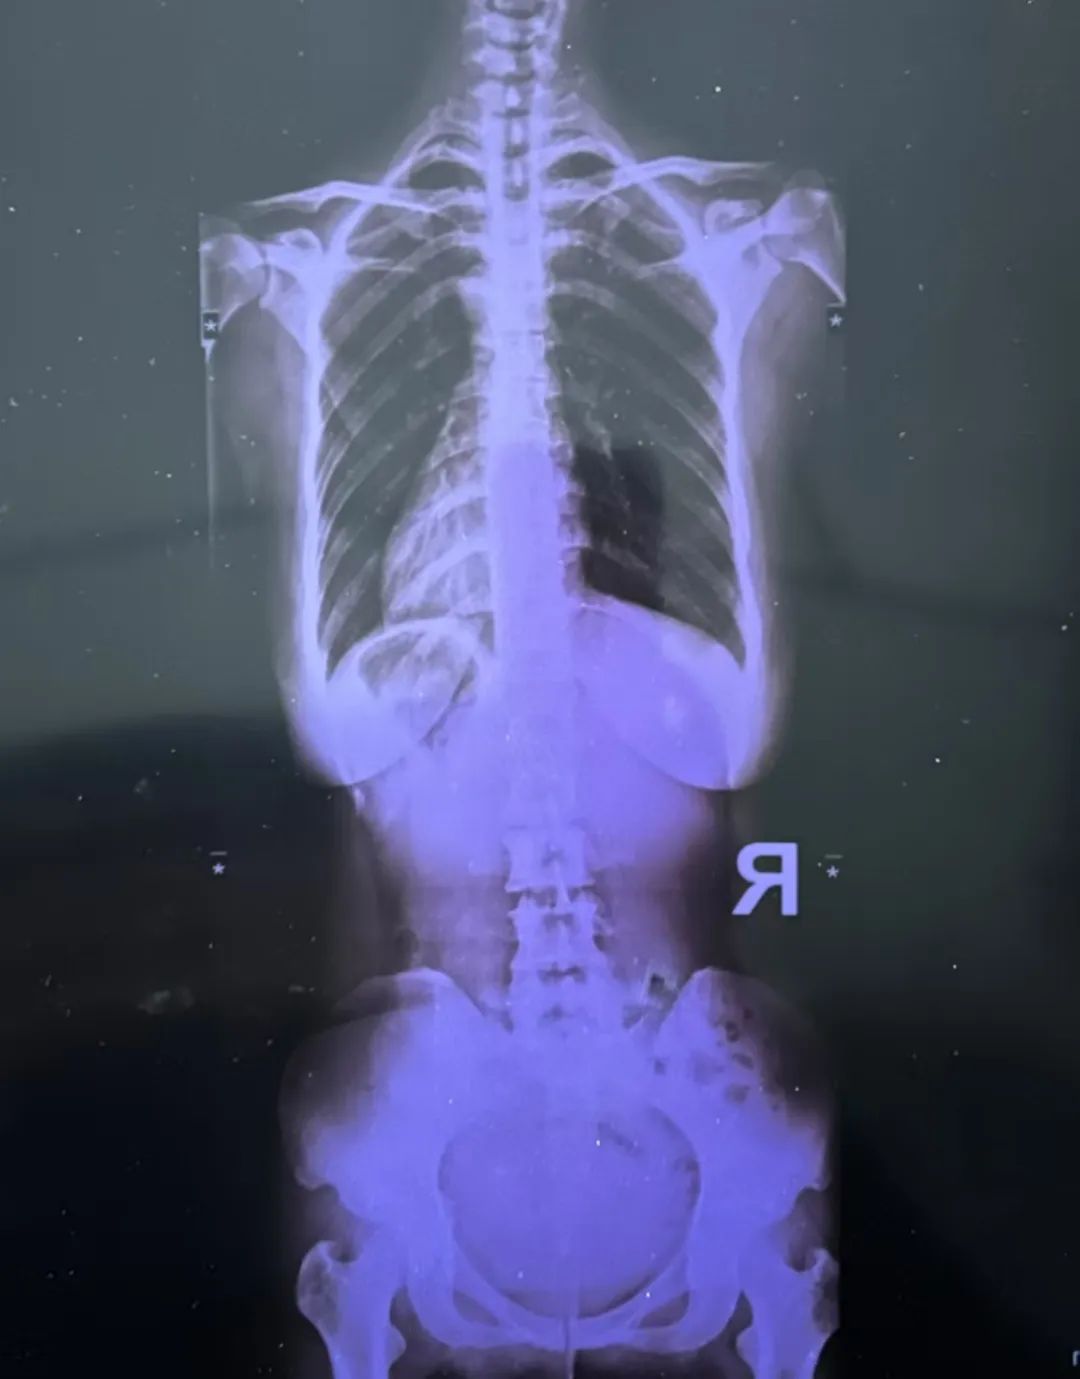

最近又疼起來嚴(yán)重影響正常生活,她前往醫(yī)院就診,結(jié)果查出了脊柱側(cè)彎11°,盆旋移,骶髂關(guān)節(jié)半脫位,由于這些導(dǎo)致頸肩,后背,腰部肌群代償出現(xiàn)問題,從而出現(xiàn)腰痛,后背痛,肩膀痛!

75.jpeg

76.jpeg